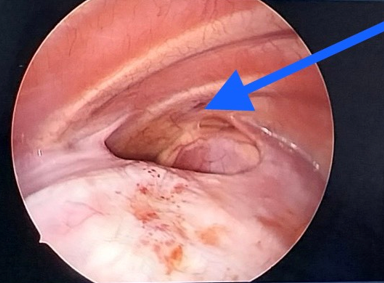

Hình 2: Hình ảnh các quai

ruột chui lên lồng ngực qua lỗ thoát vị hoành P